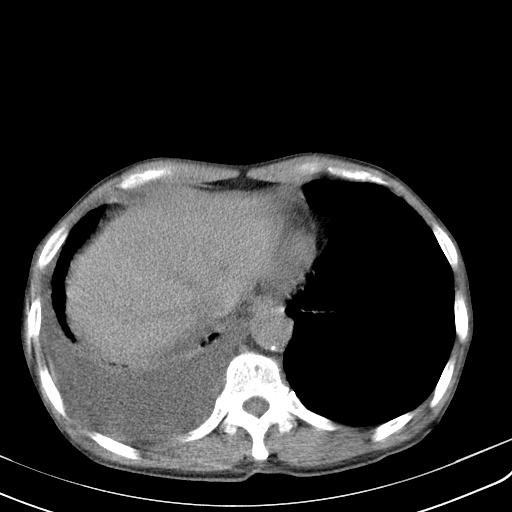

男性 75  咳嗽 一周前发热最高达39

右肺继发型tb并右侧tb性胸腔炎,右侧胸腔大量积液并右下肺膨胀不全,慢支肺气肿、多发肺大泡。建议抽胸水实验室检查并复查排除恶性在占位。

右上肺继发型肺结核,右胸腔中等量积液。

结核的基础上有纵隔淋巴结肿大,右侧有胸水,但右侧纵隔反而窄,说明有肺有不张。

再就是右下肺有块影,和不张混合,还是不能除外肺癌。

补充材料,患者2月份ct片大致正常,双侧胸腔积液,2月份抽胸水未发现ca细胞,现患者发热,痰多,各气管通畅,

1)右肺继发型肺结核。2)左肺胸膜下多发性肺大泡。3)右侧胸腔积液。